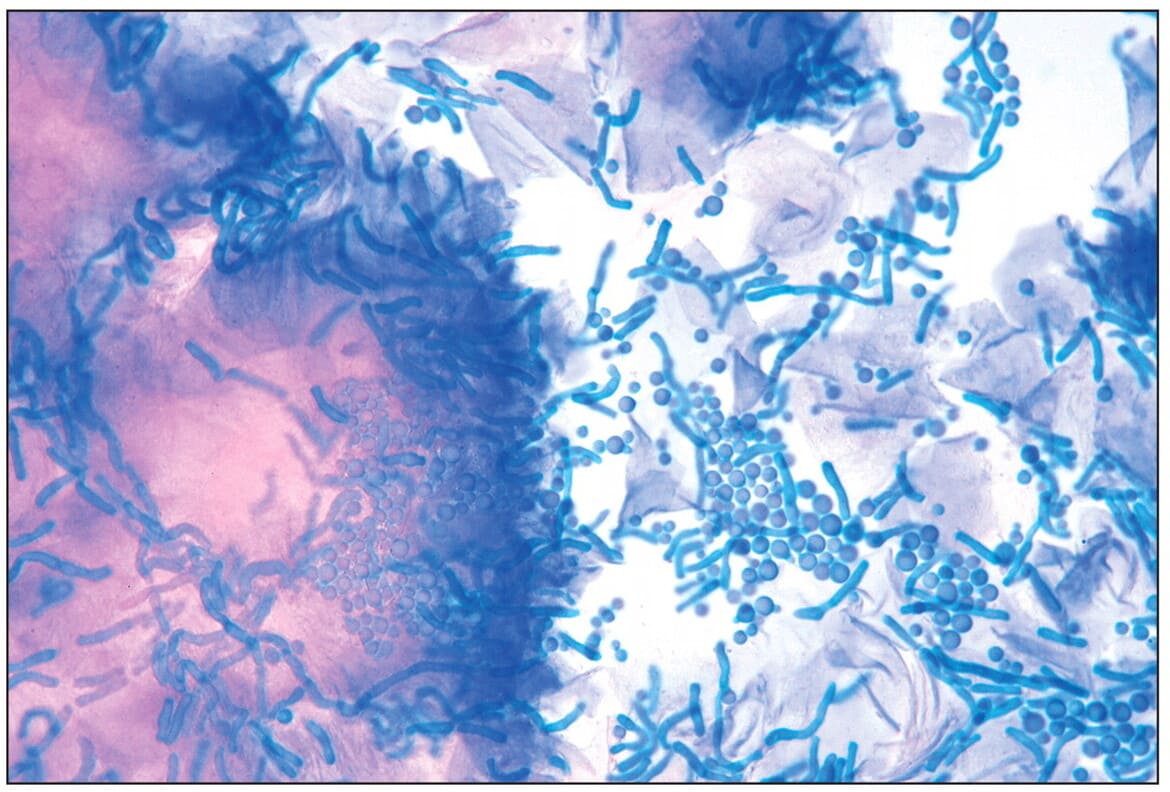

Почему появляется перхоть на голове

Перхоть — образование на коже головы чешуек (мёртвых клеток) белого или желтоватого оттенка. Считается одной из лёгких форм себорейного дерматита.

Главные причины появления:

- избыточное размножение грибка Malassezia Furfur и Pityrosporum ovale;